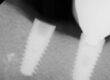

The end photographs are of a new Astra Tx aqua implant as an undamaged control. The center four images were taken from the preop impression before any recovery efforts in this office. The impression was rotated 90 degrees in each subsequent view.

What can be seen: The prior recovery effort had no possibility of succeeding, as the effort was clearly eccentric and solidly into implant structure. Any retrieval efforts could not rotate the remaining fragment up, because the extractor would be engaged into the implant as well as the screw fragment. If pursued hard enough, additional torque would result in a fractured recovery instrument. Four of the twelve indexing splines had been eliminated, but eight still remain. Eight is enough to provide a positive index for another abutment. There was no visible damage to the top 11 degree conical connection, which is the critical element that supplies the stability for the abutment to implant connection. That is good news. The problem is how much thread has been lost and is it enough to establish stable preload for the abutment screw?

What cannot be seen: Looking at the impression, the lack of impression material indicates there is still a lot of screw fragment left in the implant, both in length and on the side opposite of the damage. This area is illustrated with yellow arrows.